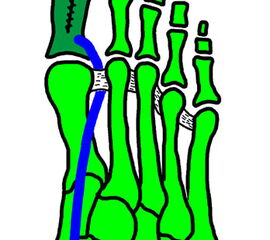

Klinisches Erscheinungsbild eines Hallux varus (eigenes Bildmaterial)

Abbildung 1

Bei einer geringgradigen Ausprägung eines Hallux varus (bis ca. 10° negativer Hallux-valgus-Winkel) sind die Betroffenen selten beeinträchtigt, in der Regel bedarf es keiner Therapie. Die Korrektur durch den Druck der Zehenkappe im Schuh ist meist bereits ausreichend.

Bei zunehmender Fehlstellung klagen die Patienten über Druckbeschwerden im Schuh, insbesondere am Endglied innenseitig oder über dem IP-Gelenk der Großzehe sowie über bewegungsabhängige Schmerzen im 1. MTP-Gelenk. Häufig sind die Betroffenen auch kosmetisch unzufrieden (Janis et al., 1975).